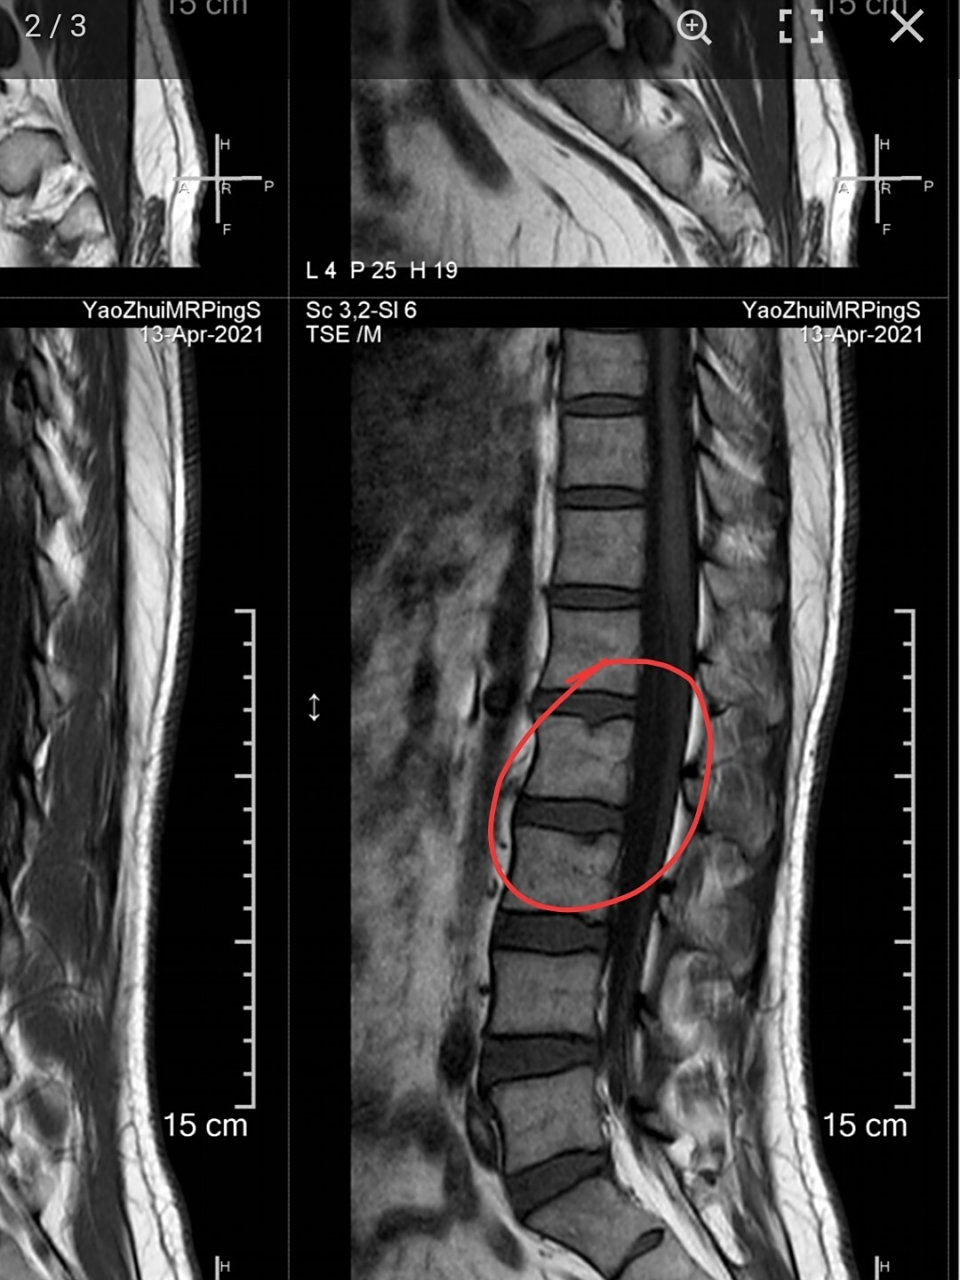

请问医生这个严重吗? 许莫氏结节

图片尺寸540x960